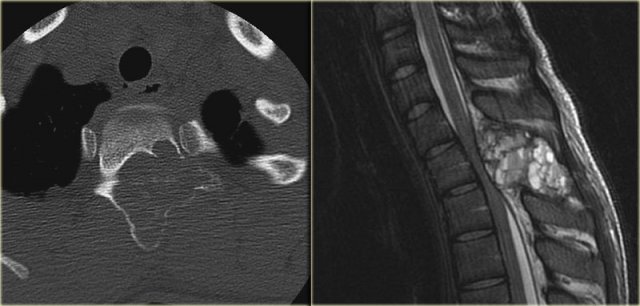

On the left a typical location for an ABC in the posterior elements of the spine.

Notice the well-defined osteolytic presentation with multiple fluid-fluid levels on MR with the patient in supine position.

The differential diagnosis based on the CT is:

ABC, Osteoblastoma and Tuberculosis (1).